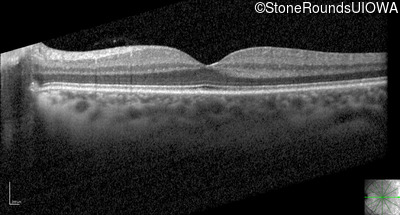

Optical Coherence Tomography - Right - 20/25 -2

Exemplar / OCT Stack